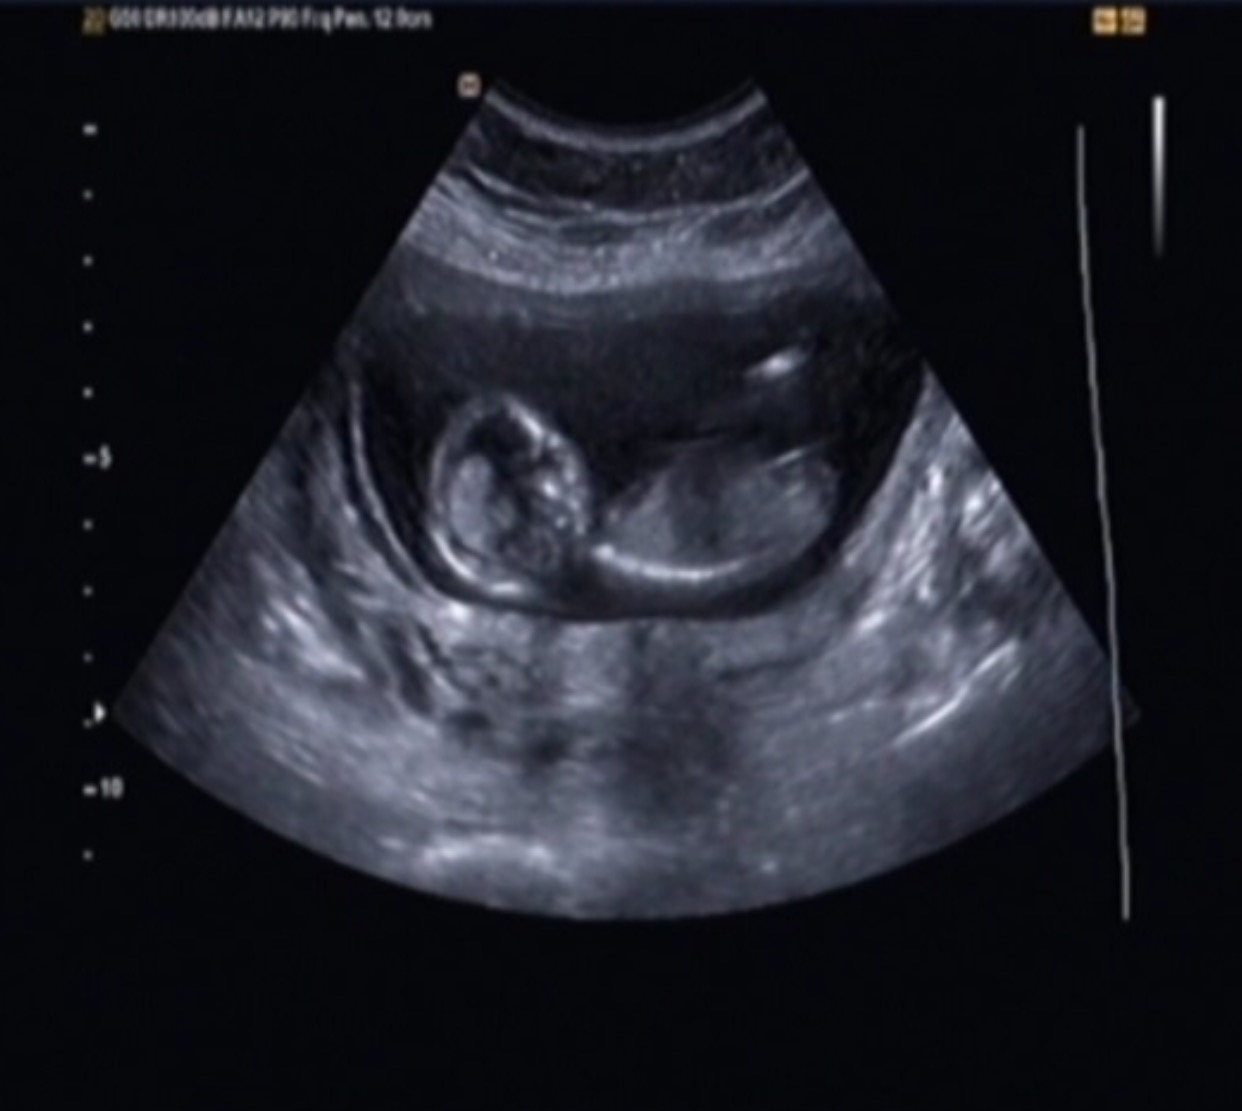

But I have had two scans, and told girl twice. Once the tech was extremely confident and said she wouldnt have said anything at all if she wasnt sure. The second tech said she was pretty sure she saw labia but our little one didnt want open her legs much at all that scan. I have pics from both scans that I want to post that include potty shots and nubs. Input?

Attachment 28271Attachment 28272Attachment 28273Attachment 28274